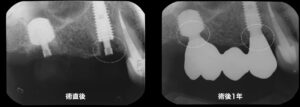

術直後と術後1年の比較写真。インプラント周囲の骨吸収はないどころか、新たな骨が新生されています。